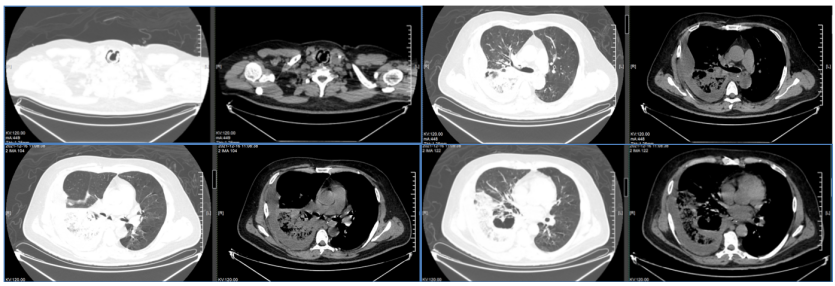

入院1周前,自觉喘累较前加重。2021年11月29日患者突发呼吸困难,伴发热,体温最高39.8℃,咳嗽、咳痰,痰中夹杂咖啡色痰液。胸部CT提示:双肺炎症,右肺下叶支气管壁增厚,部分支气管闭塞,右肺下叶后基底段多房含气腔影图1。予亚胺培南西司他丁+莫西沙星抗感染、解痉平喘化痰、降糖等治疗,后因治疗效果不佳,转我院诊治。

图片

图1  患者外院胸部CT